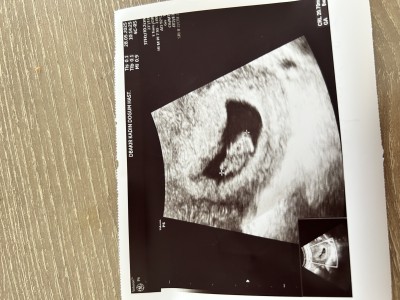

Merhaba hanımlar işin eğlencesi sizce erkek mi kız mı sağlıklı olması bizim için öncelikli tabiki ama merak işte hamile olupta merak etmiyorum diyen yoktur heralde

Gebelik haftası 8+5